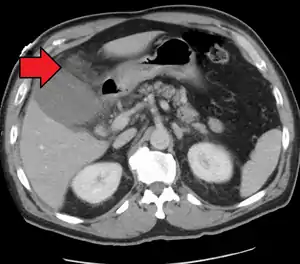

| Acute cholecystitis as seen on CT. Note the fat stranding around the enlarged gallbladder. | |

Right upper quadrant abdominal ultrasound is most commonly used to diagnose cholecystitis.[1][26][27] Ultrasound findings suggestive of acute cholecystitis include gallstones, pericholecystic fluid (fluid surrounding the gallbladder), gallbladder wall thickening (wall thickness over 3 mm),[28] dilation of the bile duct, and sonographic Murphy's sign.[13] Given its higher sensitivity, hepatic iminodiacetic acid (HIDA) scan can be used if ultrasound is not diagnostic.[13][14] CT scan may also be used if complications such as perforation or gangrene are suspected.[14]